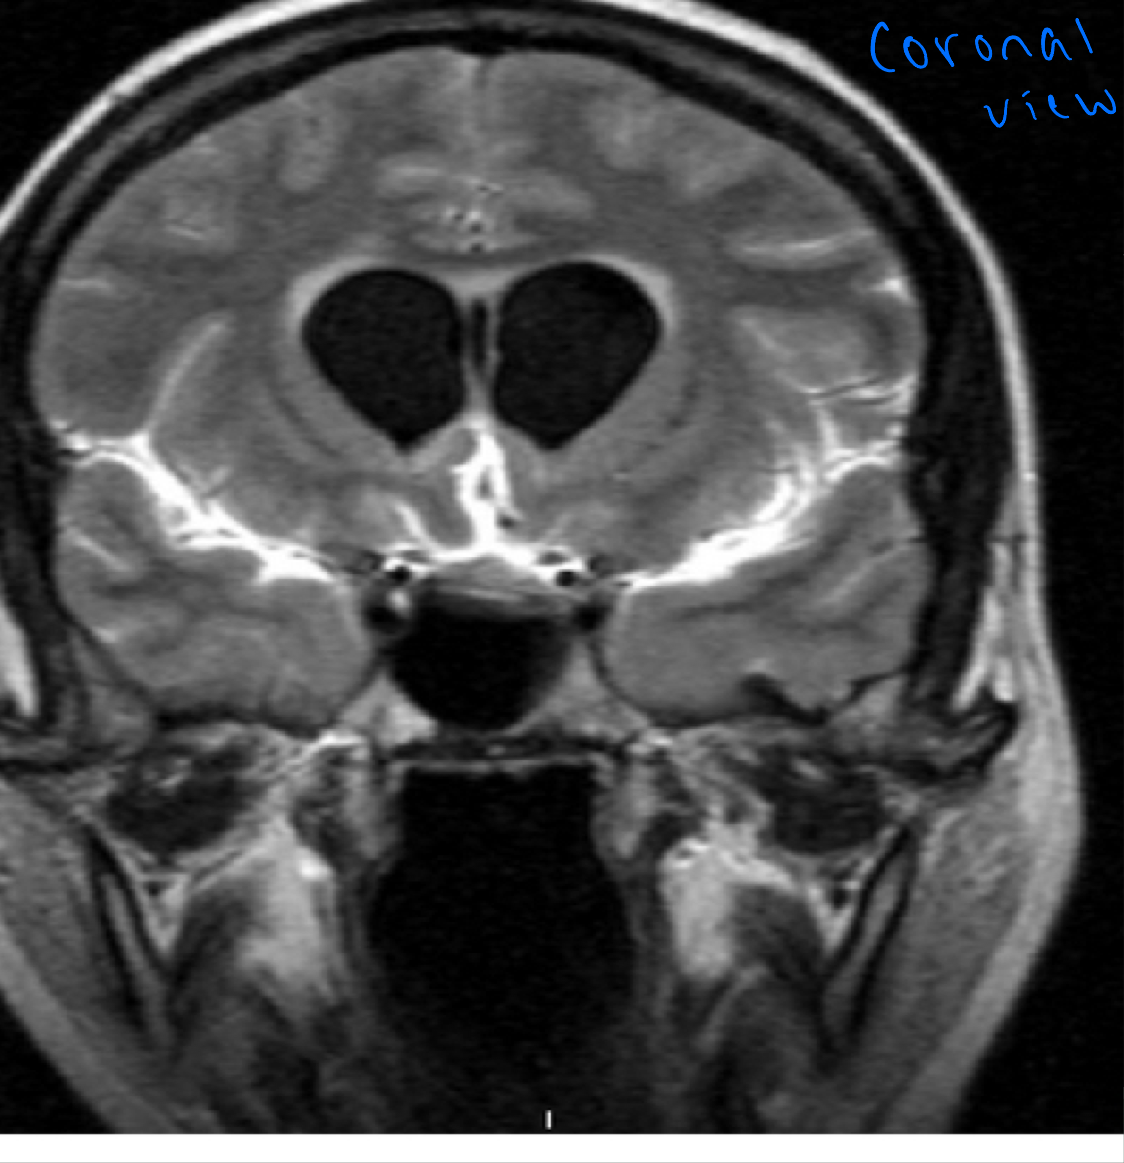

FLAIR MRI

Postcontrast. FLAIR MRI of a case of meningitis

Shows the enhancement of meninges at the tentorium and in the parietal region, with evidence of dilated ventricles